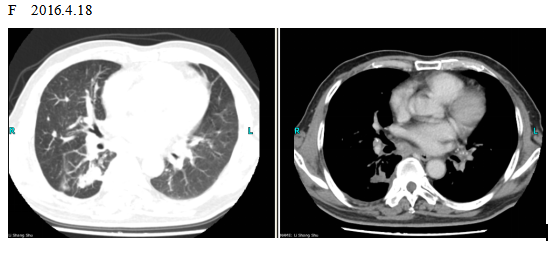

The patient checked for further treatment on November 23, 2015. A pre-chemotherapy assessment was made and the results showed multiple bone metastases and multiple enlarged lymph nodes in the left shoulder blade, the fourth lumbar, the right iliac bone and other locations. Performance status (PS) was only one point. Pemetrexed Disodium (500 mg/m2 d1) + Carboplatin (AUC 5 d1) + Bevacizumab (7.5 mg/Kg d1) was administered beginning November 26, 2015 for the chemotherapy treatment and supportive therapy was provided, such as, dehydration, reduction of intracranial pressure, promotion of bone repair, pain relief, and waist protection. After discharge, the coughing basically disappeared and the dizziness, backaches, and hemiparesthesia of the left side were significantly improved. Patient emotional state and sleep quality was significantly improved. It was basically normal after a routine blood examination. A second chemotherapy treatment was successfully completed on December 18 (the program is idem). The patient returned to the hospital on January 6, 2016 and was proposed for a third chemotherapy. The pre-chemotherapy assessment showed that the measurable, targeted right lung lesion had decreased (3.2 mm, with a rate of decrease 44.8 %) (Fig. 1D). Lymphangitis carcinomatosa was significantly decreased and right frontal nodulus lesions were reduced significantly (Fig. 2C). No new lesions were found. Efficacy was assessed as partial relief (PR). A third and fourth chemotherapies were completed on January 9 and January 30, 2016. Efficacy was re-assessed as PR (Fig. 1E) with lung CT review as an outpatient on February 11. Since then, the patient had been subjected to a combined administration program of pemetrexed disodium (500 mg/m2 d1) + bevacizumab (7.5 mg/Kg d1) for continued chemotherapy. A lung CT and a cranial MRI were peformed on April 16. The results showed that the control of lung lesions and intracranial lesions were basically the same as before (Fig.1F and Fig. 2D). The patient had no cough, backaches, or hemiparesthesia and the quality life significantly improved. PS was decreased to zero.